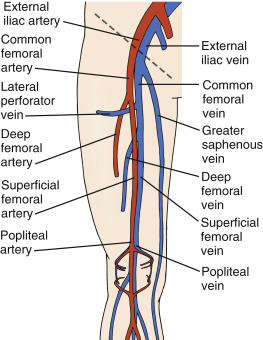

venous anatomy thrombosis superficial veins deep health sources trusted

vein thrombosis deep venous thromboembolism treatment prevention femoral common thrombus distal proximal knee ppt secondary powerpoint presentation

venous dvt deep thrombosis lower extremity system evlt